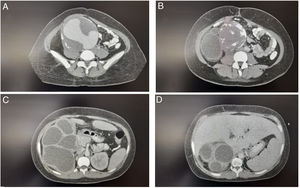

Caso clínicoPaciente mujer de 38 años de edad, quien acude al servicio de urgencias de un hospital de nivel III de complejidad, por dolor abdominal en el hipocondrio derecho, tipo cólico, sin irradiación, en la escala subjetiva del dolor 6/10, asociado a leve ictericia en escleras, náuseas y emesis en 3 ocasiones hace 4 días. No refiere otros síntomas. En el historial médico sin antecedentes destacados. Al examen físico con signos vitales estables (presión arterial: 110/70mmHg, frecuencia cardiaca: 78 latidos/minuto, frecuencia respiratoria: 16 respiraciones/minuto, saturación de oxígeno: 90%, temperatura: 37°C). A nivel cefálico; leve ictericia en esclerótica, y en el abdomen; dolor en hipocondrio derecho a la palpación superficial y profunda, sin irradiación, signo de Murphy positivo y masa en hipogastrio, pulsátil, no dolorosa, sin signos de irritación peritoneal, sin signos de respuesta inflamatoria sistémica. El resto del examen físico fue negativo para otros hallazgos. Los análisis de sangre muestran leucocitosis, función hepática y renal alterada y bilirrubina elevada (tabla 1). Ante este escenario por masa en hipogastrio, se solicita ecografía de abdomen completo, iniciando líquidos por deshidratación moderada y vigilancia clínica. La ecografía abdominal reveló una bolsa hidronefrótica derecha y una masa heterogénea en fosa iliaca derecha mal delimitada, por lo que se decidió realizar una tomografía axial computarizada (TAC) para determinar la naturaleza de la masa (fig. 1). La TAC muestra dilatación aneurismática que compromete la arteria iliaca común derecha con un trombo mural excéntrico y calcificaciones en su pared (fig. 2). Se valora por cirugía vascular que considera arteriografía de los vasos abdominales para establecer la anatomía del aneurisma. Se procede a realizar la intervención quirúrgica, en los hallazgos intraoperatorios se observa un aneurisma gigante de 10cm en la arteria iliaca común derecha con proceso inflamatorio retroperitoneal, asociado a riñón atrófico, múltiples quistes con líquido turbio en cavidad peritoneal del cual se tomaron muestras para Gram y cultivo. El servicio de urología decidió realizar una nefrectomía derecha amplia con ligadura del uréter severamente dilatado, se presume que el tamaño del aneurisma provocó la hidronefrosis severa. Se realiza un lavado peritoneal abundante de la cavidad contaminada hasta drenar líquido claro. En el mismo tiempo operatorio, cirugía vascular realiza resección del aneurisma preservando la bifurcación hipogástrica, con reparación por injerto aortofemoral autólogo con endarterectomía, ligadura u obliteración de la zona iliaca, más disección de los vasos retroperitoneales, rafia de la vena cava a nivel de las venas lumbares dilatadas, ligadura de múltiples vasos intraabdominales. Además, para la extracción del injerto de la vena safena mayor se ejecuta ligadura de vasos arteriales y venosos suprarrotulianos del lado derecho con disección de la vena femoral. El injerto fue impregnado con antibiótico por desajuste de los vasos nativos.